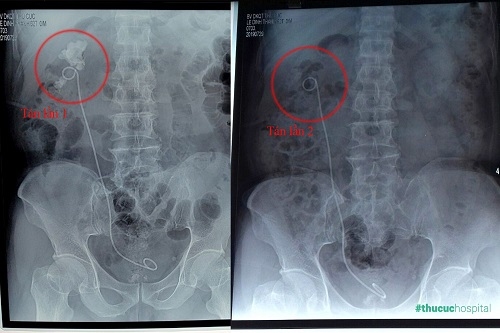

Hình ảnh khối sỏi “khổng lồ” 7cm trong thận phải của bệnh nhân L.Đ.Thanh (62 tuổi, Hà Nội).

Bệnh nhân L.Đ.Thanh (62 tuổi) tìm đến Bệnh viện Đa khoa Quốc tế Thu Cúc với tình trạng rất phức tạp. Phim chụp CT cho thấy thận tráiphải có sỏi to, kích thước 7 cm, sỏi phân nhánh, lấp kín các đài bể thận. Bác sĩ CKII Phạm Huy Huyên (Phó Giám đốc – Trưởng khoa Ngoại của Bệnh viện Thu Cúc) xác định đây là loại sỏi san hô rất hiếm gặp, đặc biệt kích thước rất lớn. Bình thường sỏi thận khoảng 2cm đã được xếp vào loại to nhưng sỏi của bệnh nhân Thanh lớn hơn gần nhiều lần. Tiền sử 2 lần mổ lấy sỏi cũng là vấn đề đáng lo ngại. Nếu tiếp tục mổ mở để lấy sỏi như trước đây, người bệnh có nguy cơ gặp phải nhiều biến chứng nguy hiểm, chưa kể vết mổ dính cũng sẽ gây khó khăn cho bác sĩ trong quá trình phẫu thuật. Tuy nhiên nếu không điều trị sỏi sẽ tàn phá các nhu mô thận, làm mất chức năng thận, có thể phải cắt thận.